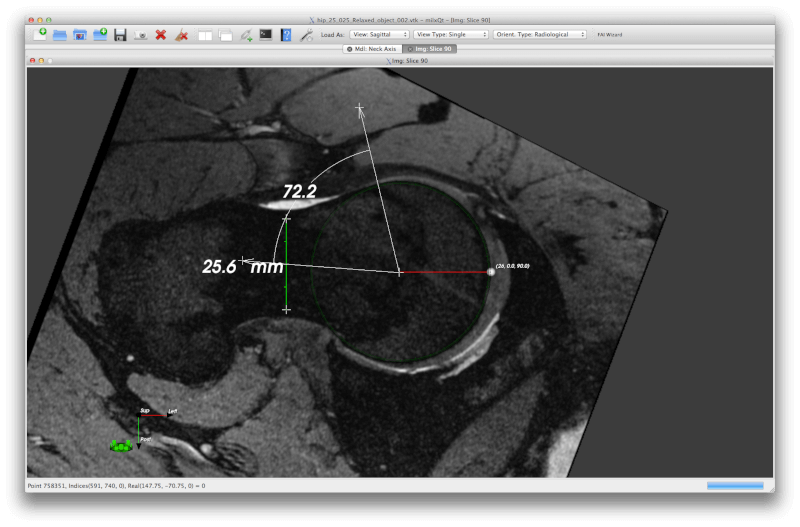

7. Mango

Mango stands for Multi-image Analysis GUI and it provides tools for image analysis coupled with a convenient GUI for navigation.

It can be used for ROI editing, image stacking, statistical analysis, surface rendering, etc. You can also customize filters, colour tables, file formats, work with plugins, and analyse other image formats such as MINC, NEMA-DES, NIFTI and NIFTI2.